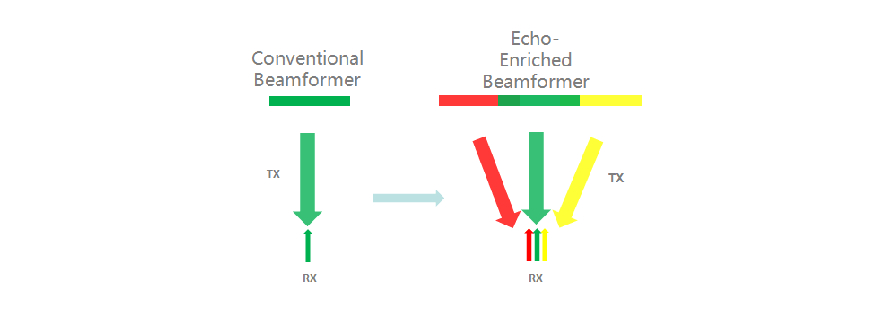

Echoverst?rkte Strahlformung

Der echoverst?rkte Strahlformer erschlie?t die traditionell nicht beachteten Echosignal benachbarter Strahlen, um einen einzigen, d├╝nneren und zugleich st?rkeren Bildstrahl zu formen, was die Aufl?sung jenseits des Fokus vergr??ert und f├╝r tiefere Bildpenetration sorgt.